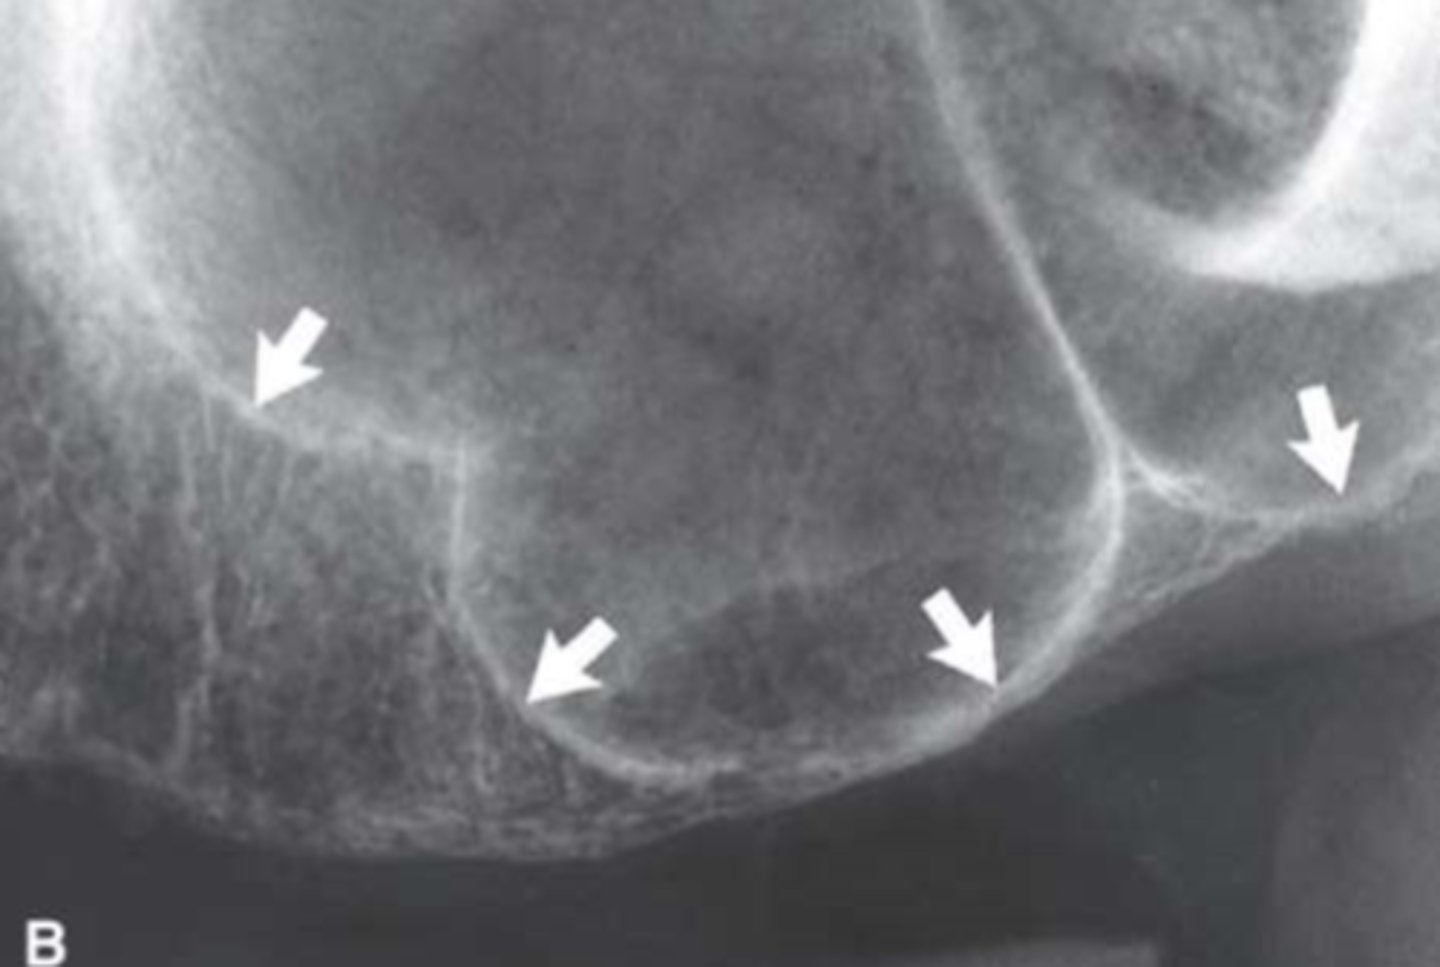

Nasopalatine (incisive) foramen

Identify the round, ovoid radiolucent structure indicated by the black arrows.

Nasopalatine canal

Identify the straight, radiopaque lines indicated by the white arrows.

Superior foramina of the nasopalatine duct

Name the two round radiolucencies indicated.